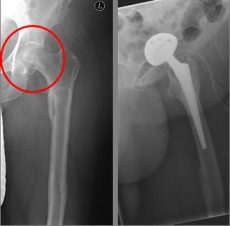

Images: Here is the supply of a dynamic hip screw shown.

In older age and with stronger displacement of the fracture can be done by a duo-head prosthesis. Here only the femoral head is replaced, the hip socket is preserved. In case of simultaneous hip arthrosis, a total endoprosthesis (hip replacement) with replacement of the acetabular cup can be used.

Picture: This picture shows the treatment of a severely displaced fracture with a so-called duo head prosthesis. The acetabulum was left here.